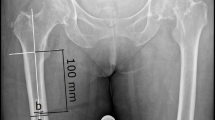

Whereas most of the fractures (86.5%) were in the diaphyseal segment (as defined in the 2018 AO/OTA Fracture and Dislocation Classification Compendium)6, it is worth mentioning that 50 (13.5%) of the fractures were in the proximal and distal end segments (Table 1). We were able to achieve stable fixation and satisfactory outcome in these end segment fractures by combining the SIGN IM nail with side plates provided by SIGN Fracture Care International (Figs. 3, 4 and 5). All but one of the humerus fractures treated were in the diaphysis and they were mostly simple (12-A) or intact wedge (12-B2) fractures (Table 2). The femur and tibia fracture patterns were similarly majority diaphyseal fractures but also having fairly high proportions among femur fractures were 31-A3 (intertrochanteric [reverse oblique]) fractures and 32-C3 (multifragmentary fragmentary segmental fractures) (Table 2).

Although the surgeries were done without intra-operative imaging, we aimed to achieve close reduction or finger reduction of the fresh fractures, and we achieved this aim in 156 cases which is 57.8% of the 270 fresh fractures (Table 1 and Fig. 2). This differs from a number of earlier studies in developing countries where reduction is mostly open in the absence of image intensifier11,12,18,20. The factors which from our observation facilitated this included: operating the fractures within 72 h of occurrence; using the retrograde approach for mid-shaft and distal femur fractures; using the Alaska Surgical Support Triangle for femur and tibia fractures. Hence, well above one-half (58.4%) of the fractures were operated within one week of occurrence and, contrary to what is reported by some previous researchers12,17,18, more of the femur fractures were operated using the retrograde (116) than antegrade (105) approach. Nevertheless, we should mention that close reduction was achieved for some of the femur fractures fixed using the antegrade approach, too.